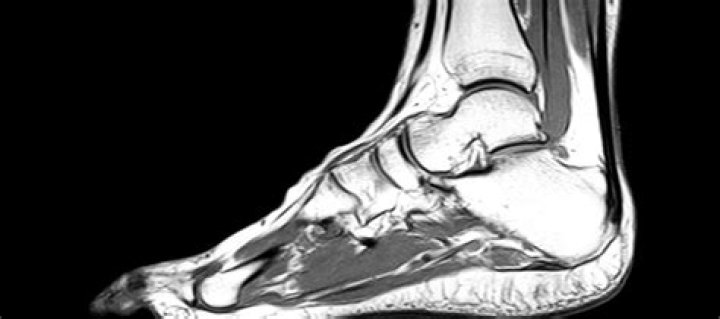

What is included in MRI of ankle?

What does MRI of foot and ankle show?

During a foot and ankle MRI procedure, pictures–also referred to as slices–of the ankle and foot will be produced. A radiologist will use the resulting images to identify any abnormalities. Such as tendon tears, inflammation, cartilage deterioration, or tumours.